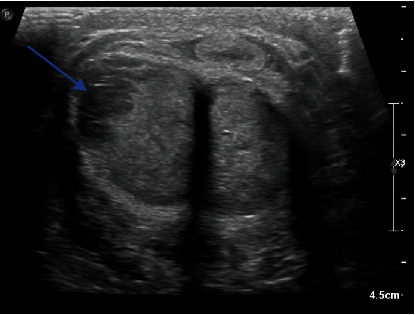

Background: The penis is a relatively uncommon organ for metastases. Secondary lesions often originate from the bladder, prostate, or rectosigmoid cancers. Only a few cases have described penile lesions secondary to lung cancers, mostly as a later complication. Case Description: We hereby report the case of an 86-year-old male patient who presented with a 3-week-long nonpainful priapism. A penile Doppler ultrasound and a chest and abdominal CT scan were performed, showing a left hilar lung mass as well as lesions in the liver, the adrenal glands, the pancreas, bone structures, and the penis. Penile metastasis is associated with a poor prognosis because of the frequent disseminated malignant lesions in other sites. Conclusion: Malignant priapism should be suspected, especially in patients with no evident risk factors for priapism (hematological diseases, drugs, alcohol, neurological diseases, or metabolic disorders).